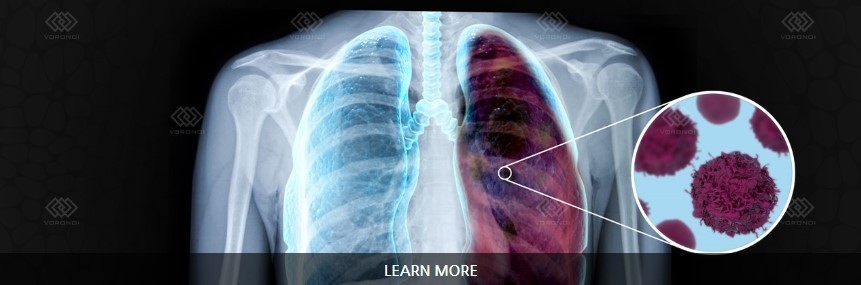

오늘은 우리 몸의 호흡을 책임지는 폐에 대해 이야기하려 합니다. 특히, 폐에 발생하는 악성 종양인 폐암의 초기 증상에 대해 자세히 알아보려 합니다.

폐암 초기증상 폐암은 초기 증상이 감기나 다른 호흡기 질환과 비슷해 간과하기 쉽습니다. 하지만 조기 발견이 치료에 매우 중요하기 때문에, 미묘한 변화라도 놓치지 않는 것이 중요합니다. 지금부터 폐암의 주요 초기 증상들을 꼼꼼히 살펴보고, 건강을 지키는 첫걸음을 함께 시작해 볼까요?

폐암 초기에는 특별한 증상이 없는 경우가 많지만, 암이 진행되면서 다양한 신호를 보낼 수 있습니다. 다음은 폐암 환자들이 흔히 경험하는 10가지 주요 초기 증상입니다.